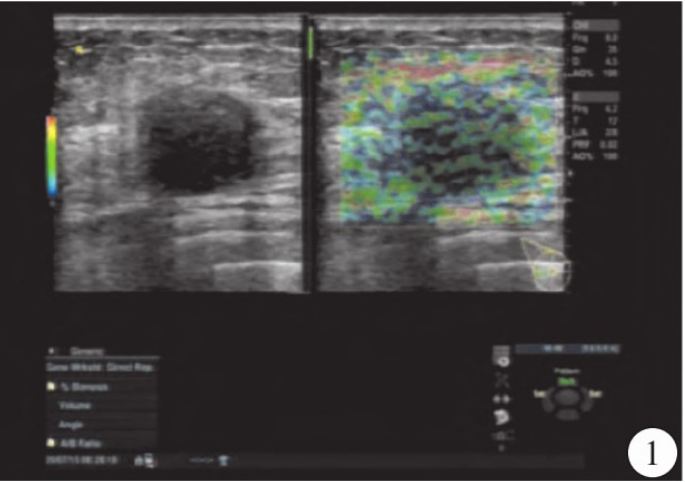

超声检查:右乳腺见大小约3.0cm×1.8 cm×2.4 cm的低回声结节,边界不清,形态不规则,呈角样改变,内见微钙化,弹性成像组织显示蓝色(图1),CDFI显示右乳腺低回声结节内见星点样血流信号(图2);右侧腋窝见约1.4cm×1.1 cm的淋巴结,门结构显示不清,右侧腋窝淋巴结内均见少许星点样血流信号(图3),诊断右乳腺BI-RADS 4c类结节,右侧腋窝异常肿大淋巴结。MRI显示右乳腺外上象限可见结节样稍长T1、稍短T2结节影,边界不清,呈毛刺状,病灶大小约2.1 cm×2.5 cm×2.1 cm,增强扫描呈环形强化(图4、5)。

图3 右侧腋窝异常肿大淋巴结,门结构显示不清,内均见少许星点样血流信号。